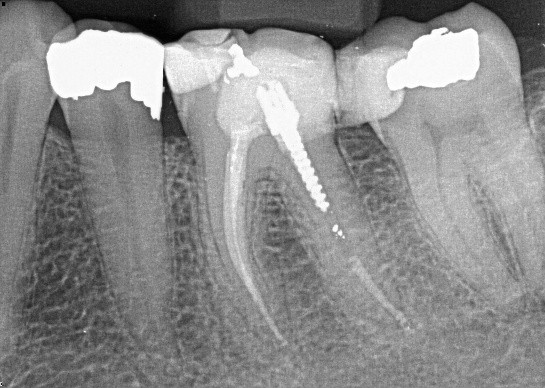

8. (Select ONE OR MORE correct answers)

Which of the following describe(s) the endodontic treatment of tooth 3.6?

9. (Select ONE OR MORE correct answers)

Which of the following describe(s) the endodontic treatment of tooth 3.4?